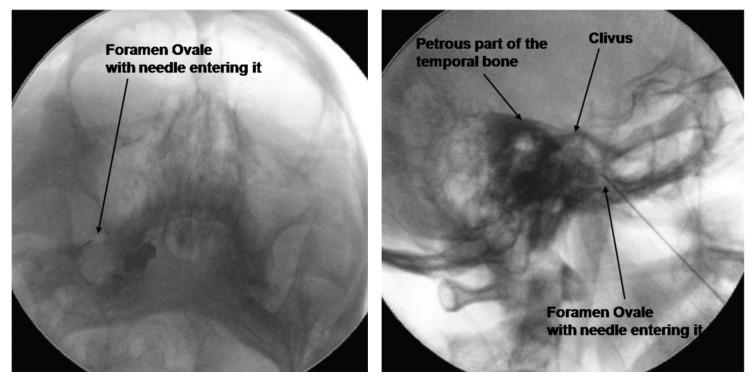

The primary objective of this retrospective study is to report the results for 36 consecutive patients who underwent PRF treatment for TN, for 6 minutes at 45 V at a pulsed frequency of 4 Hz and a pulse width of 10 ms.

For the study, we obtained procedural records of 36 consecutive patients. Their current state of pain was evaluated over a telephonic survey and the post-procedural data at 2, 6, and 12 months were retrieved thereafter from the patient records. The main outcome measure was excellent pain relief (more than 80%), which was assessed at 2, 6, and 12 months.